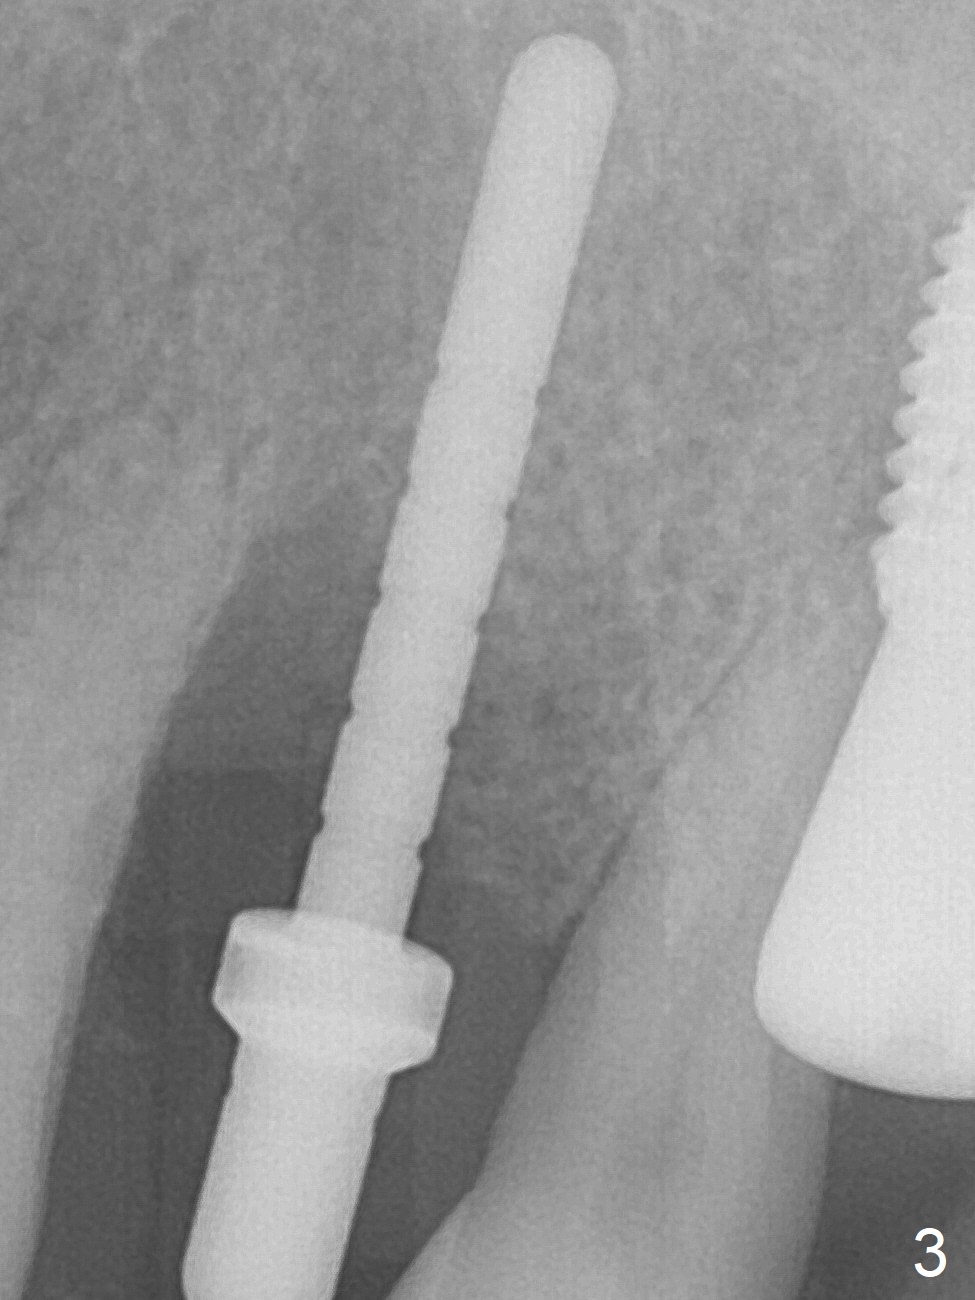

A few days prior to surgery, the tooth #12 developed abscess, self controlled by water pik (Fig.1 *). The buccal plate is defective. Initial osteotomy is close to the root of the tooth #11 (Fig.2). After adjustment of the trajectory and the depth of osteotomy (Fig.3), a 3.8x15 mm dummy implant is placed (Fig.4,5). In spite of a shorter implant (3.8x13 mm) placed deeper, approximately 7 mm implant threads are not covered buccally by the native bone (Fig.6 red dashed line). If the implant were placed deeper, the crown/implant ratio would become more unfavorable (abutment screw loosening, Fig.7). Since a mill abutment (4.5(2) mm) is inserted before Vanilla Graft, the deepest portion of the socket is unfilled (Fig.7 *). With meticulous use of a long explorer and additional allograft, the space is closed (Fig.8 *). The buccal plate collapses with apparently fistula formation 2 months postop. The patient removes the provisional for cleaning. It appears that the mill abutment is buccally placed and needs heavy reduction. The mill abutment is loose 2 months 10 days postop. When it is retightened, it tilts distal. Bone remains around the implant 6 months postop (Fig.9). Without a provisional at #12 for 5 months, the tooth #13 appears to have been shifted mesially (Fig.10 arrow). The mill abutment at #12 changes to a healing one. A lingual button is placed in the mesial surface of #13. Splinted provisional is fabricated with supraocclusion at #14 and 15 as an anchor (implants). The tooth #13 is being distalized with power chains. Limited ortho is finished nearly 2 months post banding (Fig.15,16).